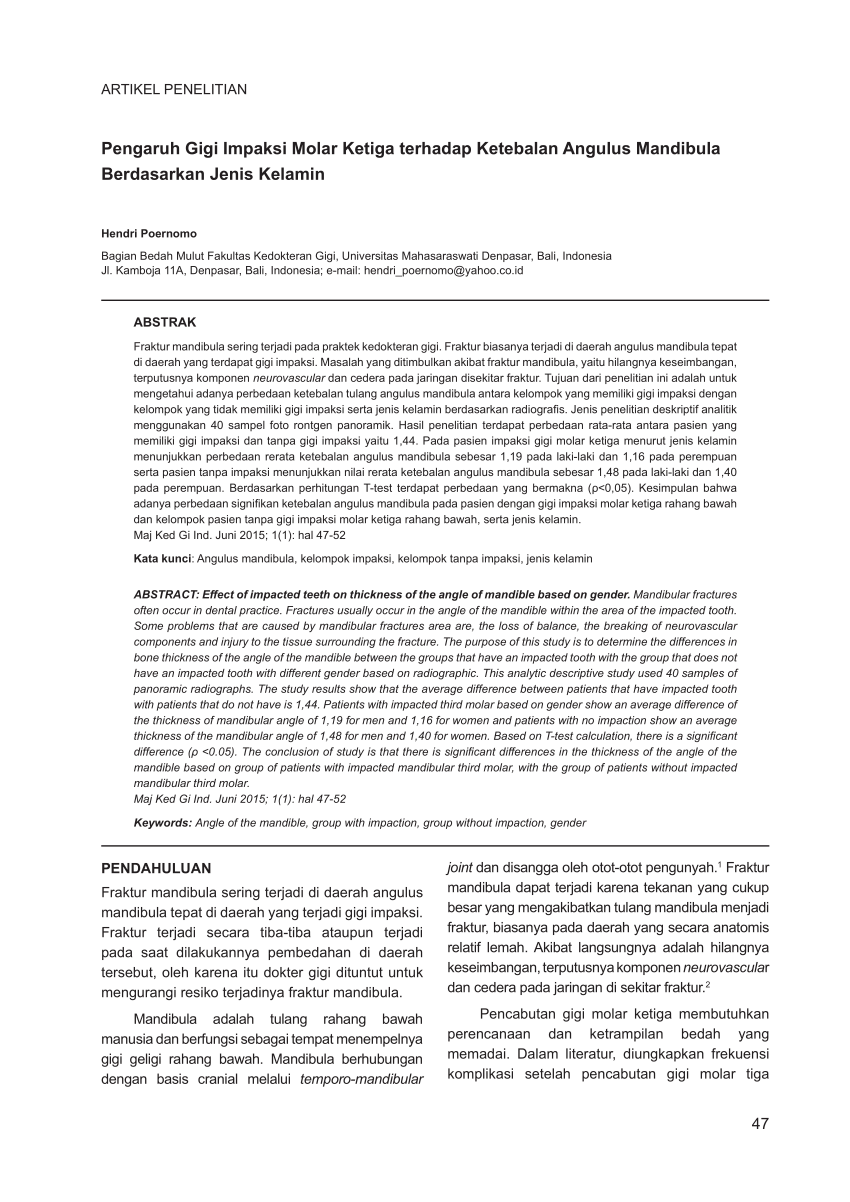

PDF) Pengaruh Gigi Impaksi Molar Ketiga terhadap Ketebalan Angulus Mandibula Berdasarkan Jenis Kelamin

PDF) Pengaruh Gigi Impaksi Molar Ketiga terhadap Ketebalan Angulus Mandibula Berdasarkan Jenis Kelamin